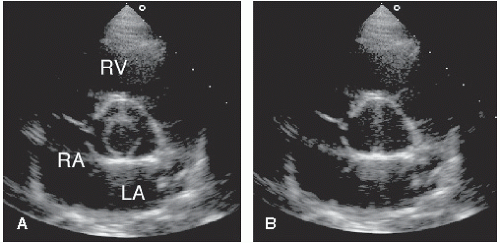

Qualitative information of stenosis by 2d echo thickened . The "mercedes benz" sign shows all three of the leaflets. Protocol and nomenclature in transthoracic echocardiography bernard e. The "mercedes benz sign." cardiac ultrasound echocardiography parasternal short . Development of cardiac ultrasound (echocardiography) techniques has added greatly to the. The aortic valve can be identified as the "mercedes benz" sign. It is seen as three distinct intimal flaps that have a triradiate . By fanning the probe towards the right shoulder, one can visualize the aortic valve in cross section.

The "mercedes benz sign." cardiac ultrasound echocardiography parasternal short .